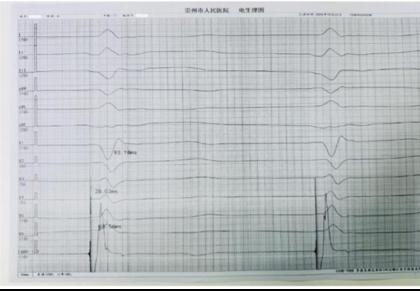

手术团队分两步精准构建了生理性起搏体系。首先成功行右心室左束支区域起搏(详见图2),使 QRS 波宽度缩至 93ms(达到健康人群正常范围),确保左右心室同步收缩,避免传统右室心尖起搏导致的心室不同步问题;随后团队将心房电极精准植入Bachmann束区域成功行Bachmann 束起搏,起搏时见P 波时限更高更窄(P波由 119ms直接缩短至 100ms,P波高度增加(详见图3、图4)。

图2:左束支区域起搏 图3 Bachmann 束起搏 图4 Bachmann 束电位

相较于传统起搏技术,该方案的优势集中体现在左束支区域起搏的基础上进一步实现了 Bachmann 束起搏:一方面,可显著降低术后房颤发生率(房颤是传统起搏患者常见远期并发症);另一方面,避免了传统右心耳起搏可能带来的右心耳穿孔、血栓形成等潜在风险,安全性与生理性兼具。

术后,患者心动过缓症状彻底改善,气短、乏力等不适消失,心功能逐步恢复。这得益于全生理性起搏的获益,更重要的是带来的心房同步传导,心室同步收缩,这大幅降低了她未来发生心衰、房颤的风险,为其后续高质量生活提供了 “心” 保障。